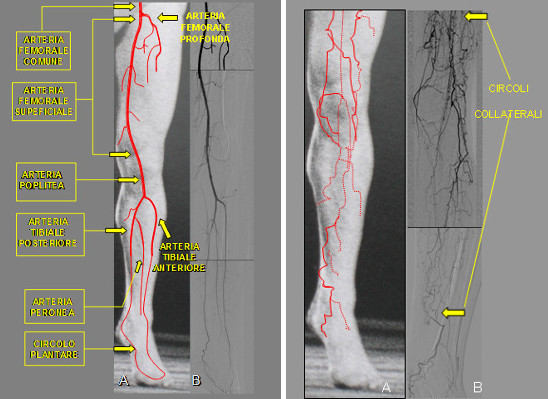

Le patologie circolatorie degli arti inferiori sono in continuo aumento per la crescente incidenza delle malattie “ostruttive- degenerative” dell’apparato cardio-circolatorio, che evolvono con l’insufficienza circolatoria e metabolica degli arti.

La chirurgia vascolare ortopedica moderna ha fatto dei passi da gigante, raggiungendo dei risultati veramente importanti per ridare “autonomia” alle persone che sono affette da patologie degenerative, che altrimenti darebbero una riduzione dell’autonomia personale oltre al disagio per il dolore. I materiali che vengono utilizzati per le protesi sono stati ottimizzati. I nuovi “invasi” in silicone termoformabili hanno migliorato il confort del paziente rendendo il protocollo riabilitativo più veloce, inoltre permettendo una mobilità sicura e “fluida”.